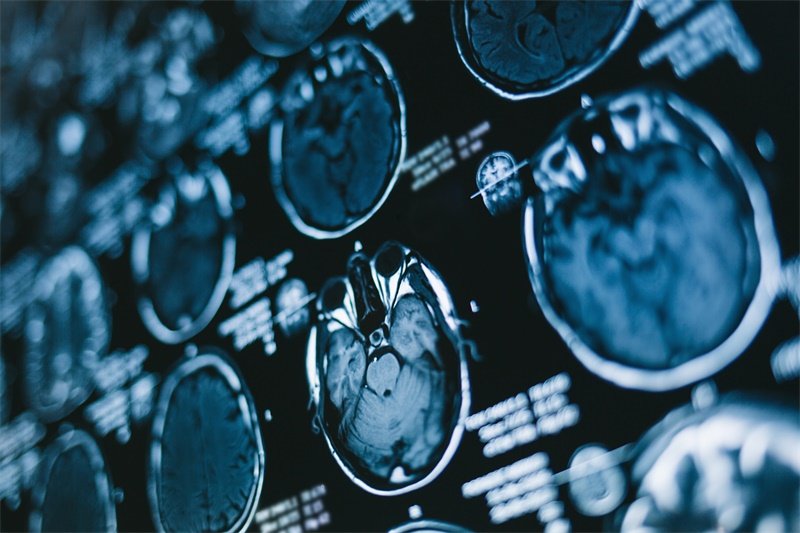

影像学检查

常用的影像学检查方法包括MRI(磁共振成像)和CT(计算机断层扫描)。这些检查可以帮助医生明确占位的性质、大小及周围结构的关系。

MRI对软组织成像效果特别好,能够清晰地显示神经结构以及病变部位。